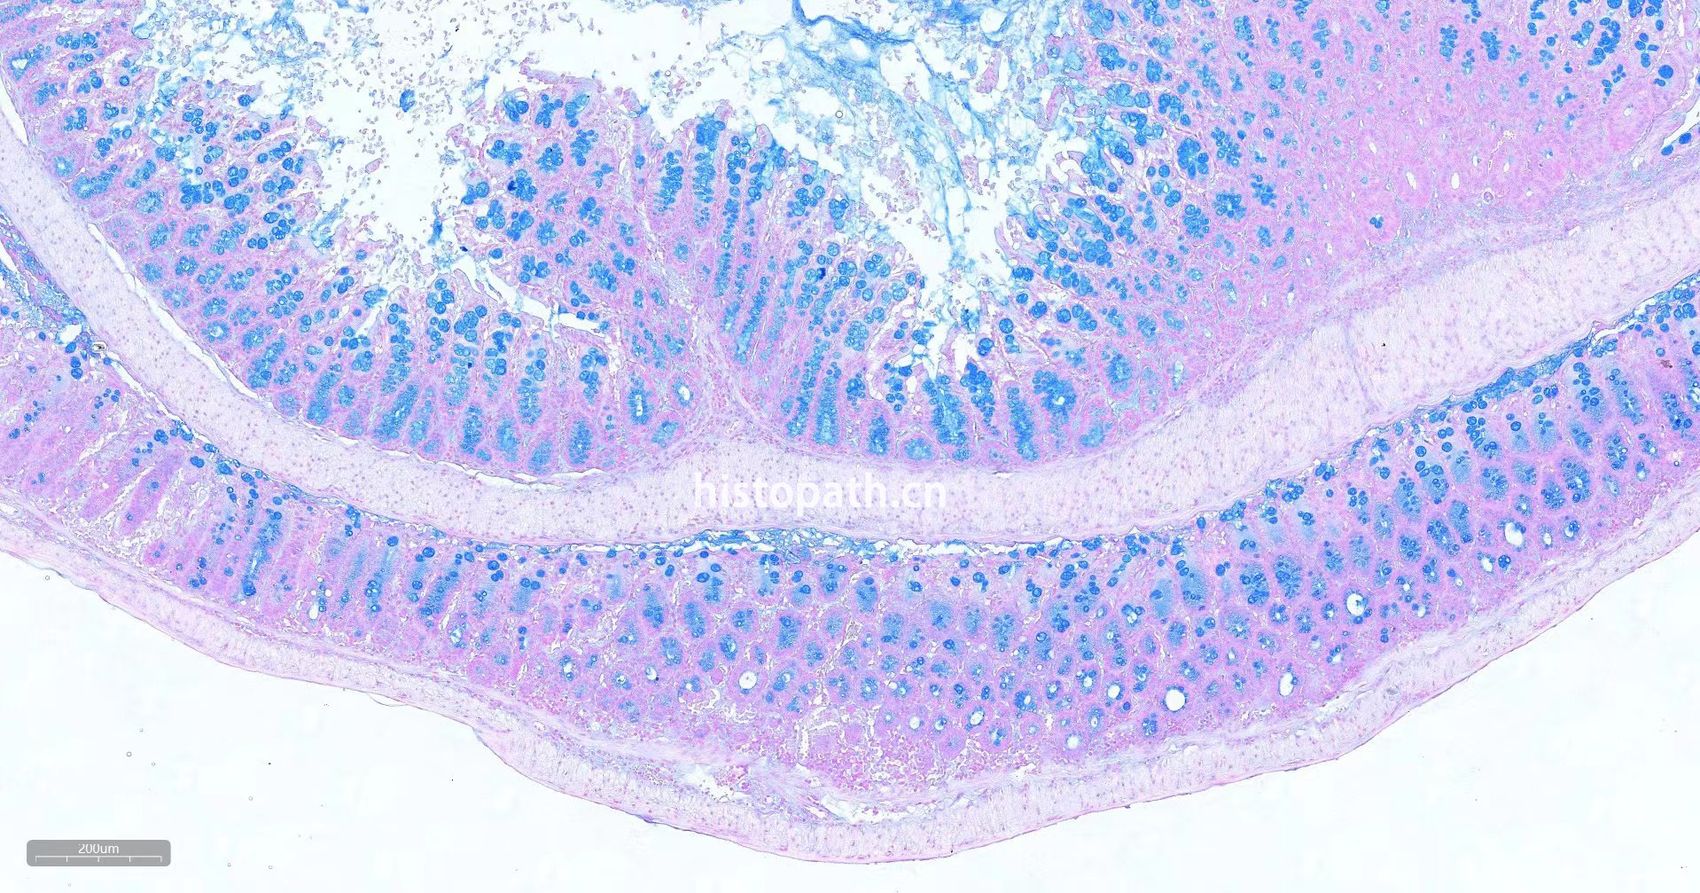

瑞士肠卷详情介绍:取5cm-7cm完整肠道正常固定后用剪刀将肠道剖开PBS涮洗干净肠道内容物后做成瑞士卷肠可观察整个肠道粘膜情况,扩大观察范围,增加切到炎症,溃疡等的几率。

肠卷阿利新蓝染色

阿利新蓝.jpg阿利新蓝.jpg阿利新蓝11.jpg